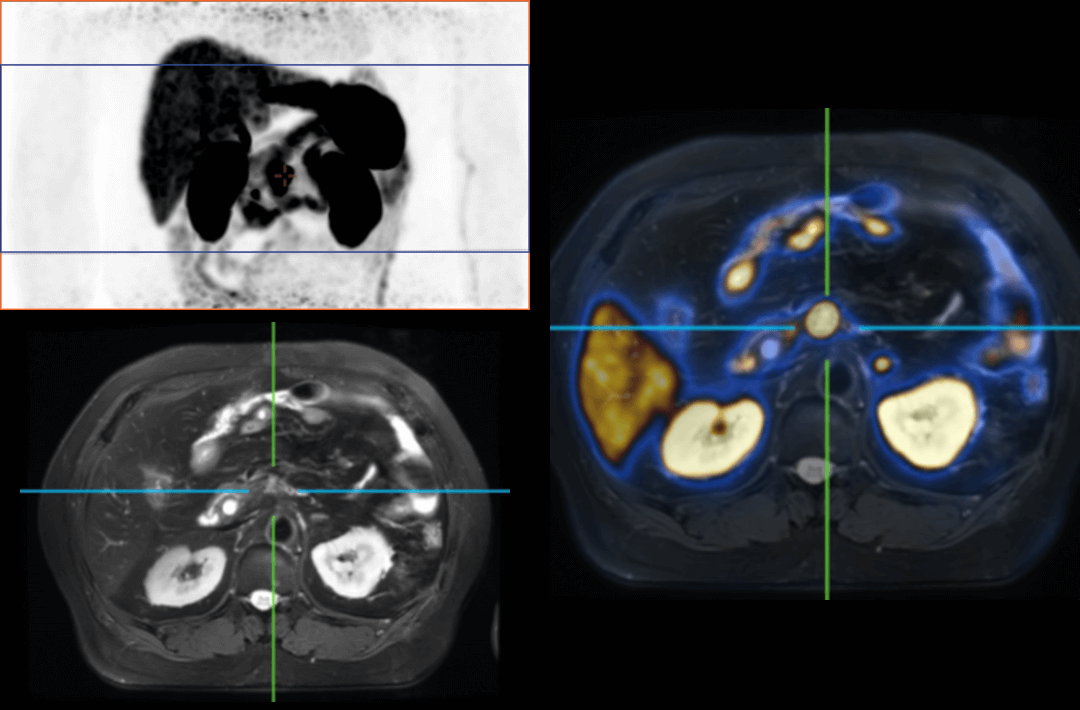

The TNM staging system is currently the most widely used staging system in the world. It can provide relevant information about the location, involvement and spread of the primary tumor through imagological examination methods. It’s one of the most important examination methods to determine cancer staging. Integrated PET/MR perfectly combines molecular functions and structural images and serves as a vital means for the clinical diagnosis of tumors, cardiovascular disease, neurological disease, pediatric disease, and inflammatory disease.

Compared with the conventional PET system with AFOV ranging between 20cm and 25cm, the 32cm long AFOV not only improves the sensitivity of the system, but also basically covers main organs of the whole body and the regional lymphatic system where metastasis may occur, and makes it possible to realize cancer TN staging in one bed position.

Traditionally, a PET/MR scan of a tumor patient takes about 35 to 50 minutes. The long AFOV can further optimize the PET/MR tumor scanning scheme. In other words, it can optimize the decision about whether to scan the whole body based on whether the tumor patient has regional lymphatic metastasis after regional PET/MR scan, potentially saving scan time for patients without metastasis.

In August 2019, Peking Cancer Hospital introduced United Imaging Healthcare's integrated PET/MR to make an in-depth exploration and optimization of cancer TNM staging under long AFOV. More than 500 examples of scanning various organs proved that long AFOV PET/MR could greatly increase the scan range over one bed position and improve the efficiency of cancer TNM staging.

The following are the cases of optimized TNM staging of breast cancer, esophageal cancer, prostate cancer and other diseases under the long axial field of "spatio-temporal integration" ULTRA-clear TOF PET/MR.  Thanks to Capital Medical University Xuanwu Medical Treatment for providing the image.